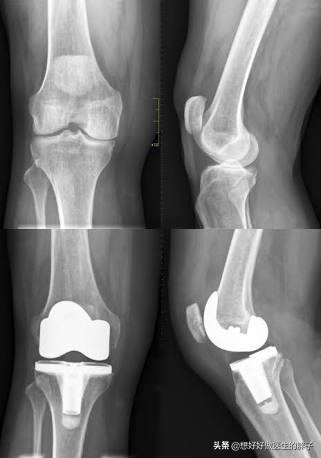

第六,手术治疗。手术治疗是医生和患者都不愿意进行的最后一步。但是有一些患者的病情确实达到了需要关节置换才能解决这些骨刺导致问题的程度。那前面已经说到了,例如肩关节、髋关节以及膝关节,如果是严重的骨质增生、严重的软骨磨损,患者会出现明显的关节活动受限,同时会伴有夜间痛以及休息痛,有的患者被折磨的痛不欲生,那么面对这种情况,可能手术治疗是最佳的治疗办法【7】。以往的手术就是比较单纯的关节置换手术,但是现在也重视到保膝手术治疗的发展,现在也有很多医生会根据患者的病情进行部分关节置换或者是截骨矫形等保膝手术治疗来尽量保留患者关节良好的部分,只处理有问题的部分。